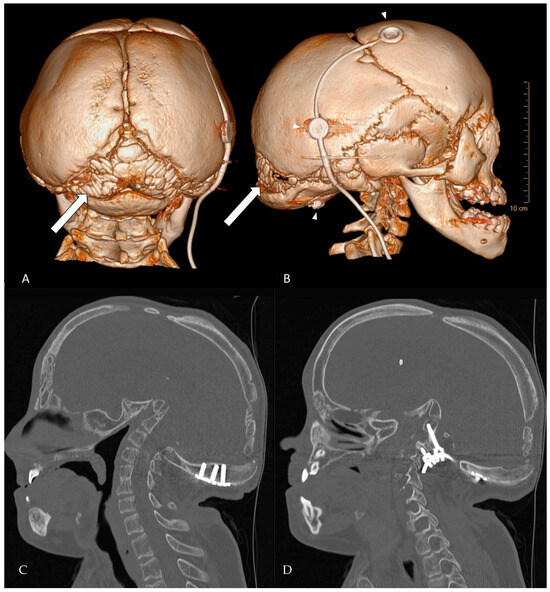

Hajdu-Cheney syndrome is associated with Wormian bones, which are indicative of osteolytic activity in the skull (Figure 2). The severity of the disease has been correlated to the number of Wormian bones. Additionally, molecular genetic testing is essential for accurate diagnosis. Given the age-dependent evolution of HCS and the potential for cranio-cervical progression, we recommend structured monitoring: (i) baseline MRI of the cranio-cervical junction at diagnosis, (ii) repeat imaging every 12–24 months during growth, or earlier if new symptoms arise (e.g., dysphagia, stridor, sleep-disordered breathing, scoliosis acceleration) and (iii) dynamic cervical radiographs or CT when instability is suspected. Routine clinical follow-up should include neurological examination, respiratory assessment and periodic bone health evaluation. A low threshold for early referral to a cranio-vertebral junction team is warranted when radiographic progression or brainstem compression is documented. Early in life, facial features may overlap (short stature, facial dysmorphism), which can delay recognition of HCS. Practical clues favoring HCS include progressive acroosteolysis, Wormian bones and delayed suture closure, cranio-cervical osteolysis with basilar invagination, generalized osteopenia and osteoporosis. By contrast Noonan syndrome typically shows characteristics cardiac lesions and lacks progressive distal acroosteolysis. In uncertain cases, targeted NOTCH2 testing confirms HCS, whereas multigene RAS-MAPK panels support or exclude Noonan spectrum disorders. This distinction matters because surveillance priorities diverge (cranio-cervical stability and bone health in HCS versus cardiologic focus in Noonan [5,8,10].

Figure 2. CT-rendering of Wormian bones at the age of 18 years. (A) posterior view of the skull. (B) lateral view. The arrows point to multiple intrasutural bone fragments arising in the lambdoid suture, a fragment can be seen in the coronal suture and pterion ossicles are present. The upper two arrowheads depict the VP-shunt system, the lower arrowhead points to a screwhead of the occipital instrumentation. (C,D) Complementary 2D bone-window CT slices (sagittal plane) detailing instrumentation the position and anatomy that are difficult to appreciate on 3D views. (C) Mid-sagittal slice showing the relationship of the occipital plate/screws to the foramen magnum and the cranio-cervical junction. (D) Left-parasagittal slice highlighting the occipito-cervical instrumentation and screw trajectory.